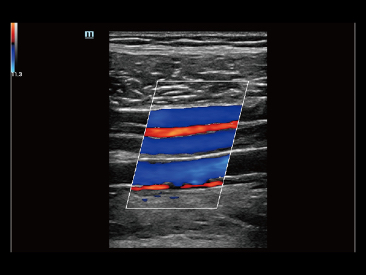

Adem├Īs de la calidad de imagen de primer nivel, Resona?7 tambi├®n mejora las capacidades de investigaci├│n cl├Łnica con el revolucionario V?Flow para la evaluaci├│n hemodin├Īmica vascular y con la adquisici├│n de planos m├Īs inteligente a partir de conjuntos de datos 3D para el diagn├│stico del SNC fetal. Al combinar el funcionamiento multit├Īctil basado en gestos m├Īs intuitivo y todas las caracter├Łsticas cl├Łnicas esenciales, Resona?7 realmente lidera las novedades en innovaci├│n de ecograf├Łas.